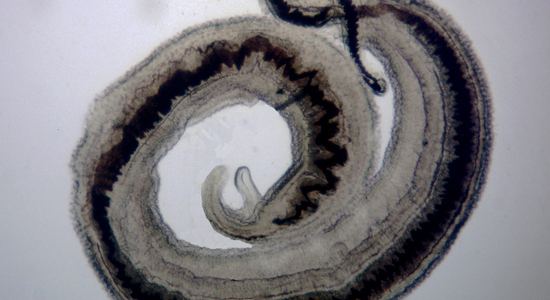

Maladies infectieuses, Vecteurs et Ravageurs: des Enjeux sanitaires pour les Humains, les Animaux et les Végétaux